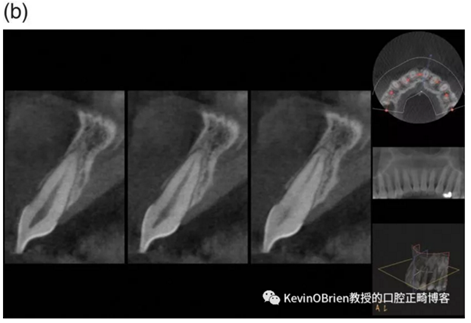

我們都熟悉正畸誘導(dǎo)性牙根吸收(Orthodontically Induced Root Resorption, OIRR)。一些研究把牙根吸收量與幾個(gè)可能原因聯(lián)系了起來(lái),例如治療持續(xù)時(shí)間,矯治器類(lèi)型以及施加的力。雖然這些研究給我們提供了有用的信息,但其大多數(shù)都采用了2D的頭顱側(cè)位X線片。CBCT影像的出現(xiàn)使得對(duì)OIRR的更精確測(cè)量成為可能。因此,作者們做了一項(xiàng)新的研究去探究這個(gè)問(wèn)題:

“用CBCT成像測(cè)量的OIRR的平均值是多少?”

總之,我覺(jué)得我們能慎重地得出結(jié)論:當(dāng)使用CBCT測(cè)量OIRR時(shí),吸收的平均值是0.6-0.8mm。這是一個(gè)令人安心的小值。